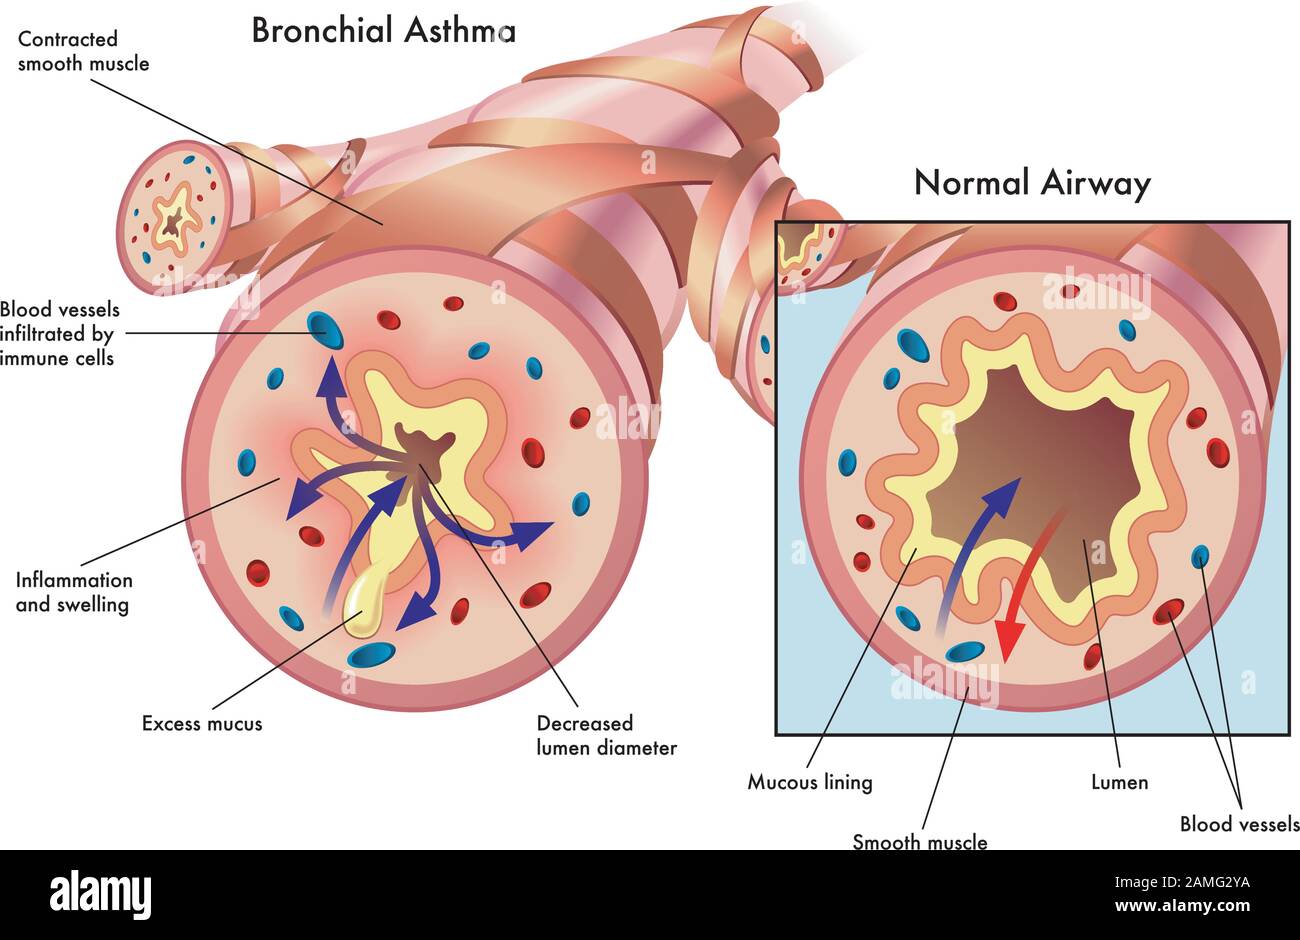

Medical illustration of the effects of bronchial asthma. Stock Vectorhttps://www.alamy.com/image-license-details/?v=1https://www.alamy.com/medical-illustration-of-the-effects-of-bronchial-asthma-image339643678.html

Medical illustration of the effects of bronchial asthma. Stock Vectorhttps://www.alamy.com/image-license-details/?v=1https://www.alamy.com/medical-illustration-of-the-effects-of-bronchial-asthma-image339643678.htmlRF2AMG2YA–Medical illustration of the effects of bronchial asthma.